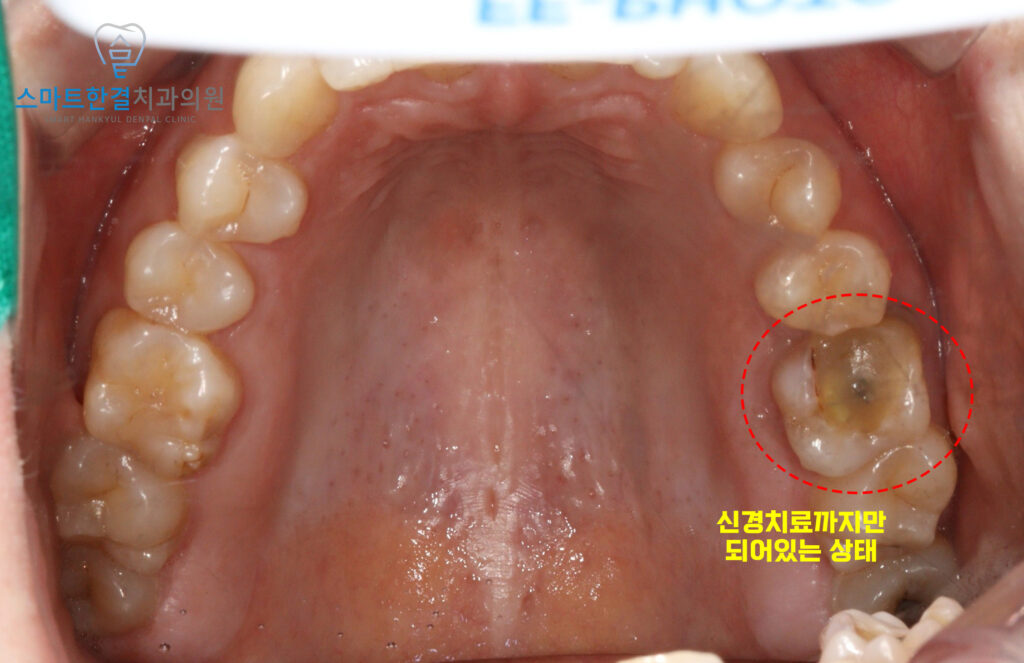

위 환자분께서는 30대 여성분으로

오래전 왼쪽 위 치아의 신경치료 후

크라운을 씌우지 않은채로 지내오셨는데요.

최근 들어 통증이 발생하고

잇몸을 누를 때 마다 불편하여

본원에 내원해 주셨어요.